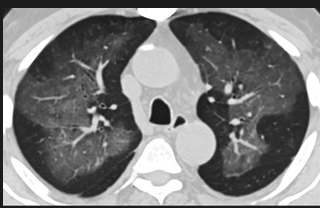

更值得注意的是,有之前应对过武汉新冠疫情的中国权威肺病专家,在查阅了60篇涉及美国“电子烟肺病”病例的研究论文,并对其中142位电子烟肺病患者的250张肺部影像图片、临床信息以及文献原文进行了仔细全面的研究后,发现这些病例中有16个更有可能是新冠肺炎的“疑诊患者”,有5个临床症状和治疗情况相对完整的患者,还被这些专家认定为了“中度可疑”。另外,这16个病例中有12个病例的发病时间,都在2020年以前。

(这4张图,是专家怀疑被误诊为电子烟肺病的其中一个病例的肺片。专家表示,他们不是仅仅通过一张影片做判断的,而是通过这4张涵盖了这名病例肺部多天变化情况的影片进行的研判,认为该病例的病程进展跟新冠更为相似)